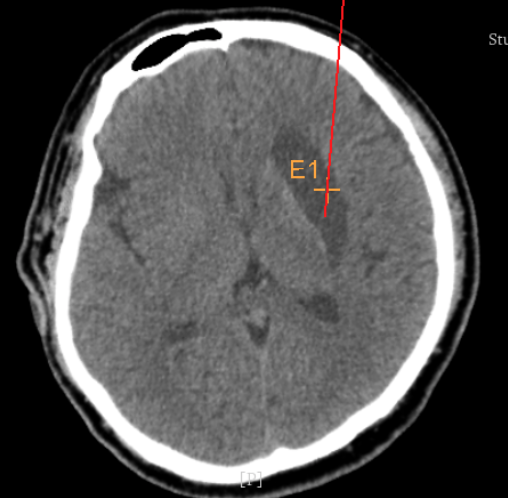

alt text

術(shù)前CT:血腫已經(jīng)液化,但仍有占位效應(yīng)